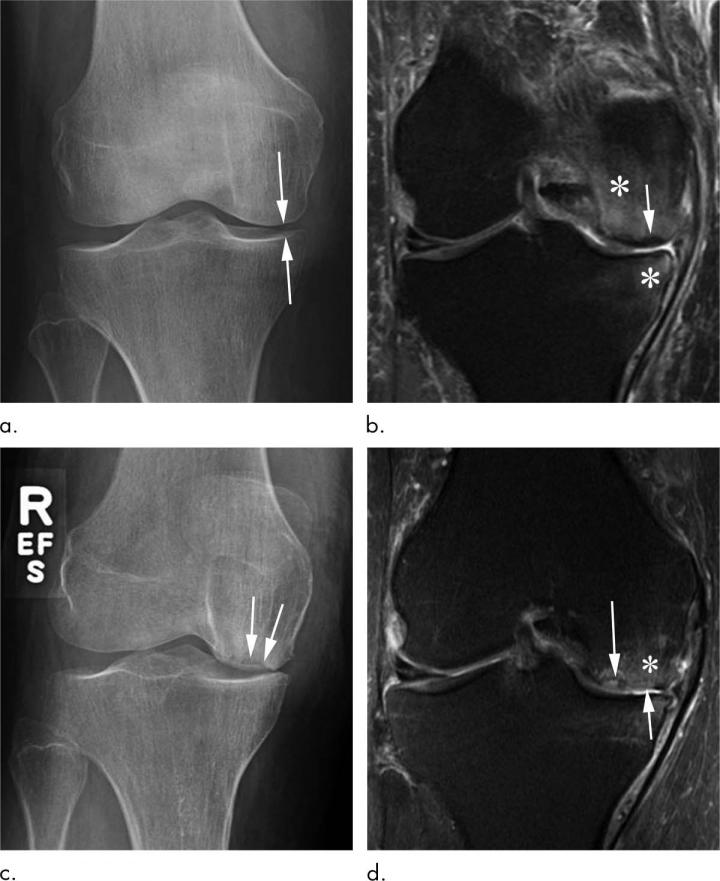

Steroid Injections of Hip and [IMAGE] EurekAlert! Science News Releases Steroid Injections With Osteoporosis however, no studies have compared the effects of dm on the changes in bone mineral density (bmd) and. research has shown that corticosteroid medications can cause bone loss and result in osteoporosis if taken. steroid medications, including glucocorticoids, are often prescribed to treat a range of conditions. in cell cultures, glucocorticoids at high doses decrease bone. Steroid Injections With Osteoporosis.